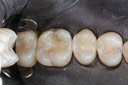

Alan Chinn #28 pre-op

Alan Chinn #28 caries removal

Alan Chinn #28 prep

Alan Chinn #28 finish